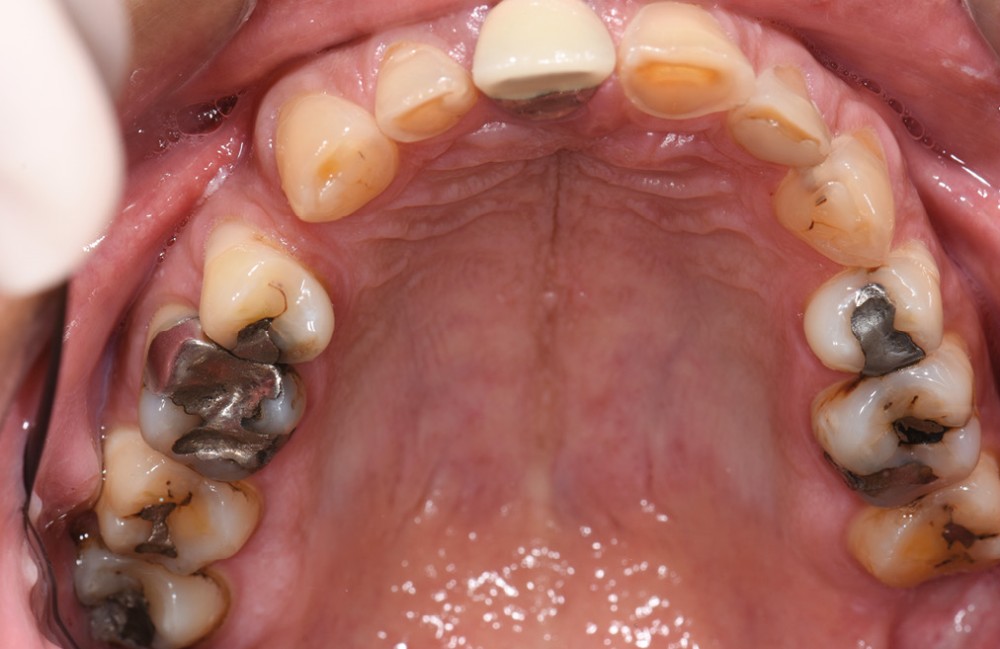

L’étiologie de cette usure est multifactorielle, revêtant une composante de type attrition (usure par contact dento-

dentaire), une composante abrasive avec un brossage traumatique et, en dernier lieu, une légère composante tribo-érosive de par une pratique importante de sport avec gel et boisson acide (fig. 1-4) [1].